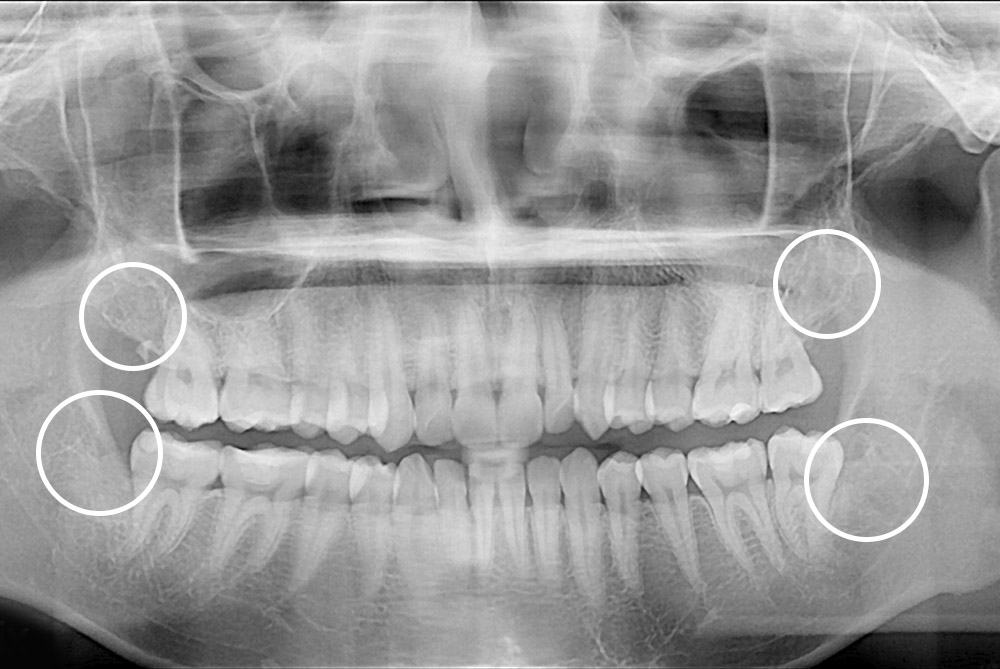

[사랑니] 매복 사랑니 발치

치료후 : 2020-08-14